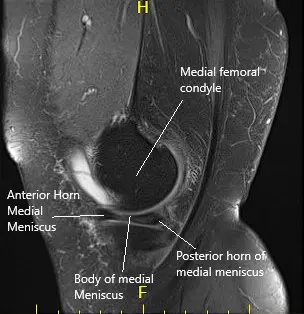

MRI of the left knee suggested a complex tear of the body and posterior horn the medial meniscus. Moderate patellofemoral chondromalacia associated moderate-sized joint effusion and capsular inflammation.

MRI of the left knee in sagittal and coronal sections.